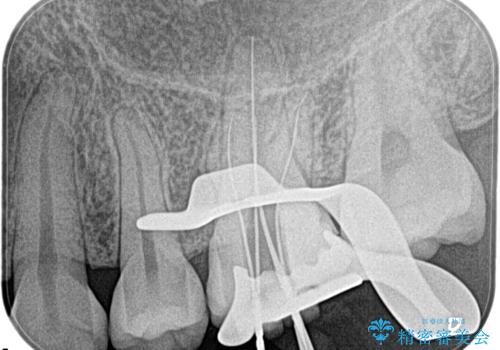

- 奥歯がズキズキ痛いことを主訴に来院されました。

検査の結果、診断を症候性不可逆性歯髄炎、症候性根尖性歯周炎とし抜髄を行っております。

主訴である痛みを解決することができました。無菌的治療を行うことで、根尖性歯周炎の予防にも期待できる治療を行いました。